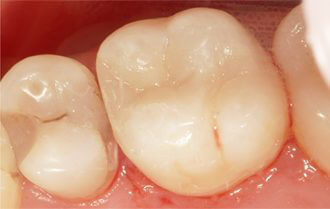

Проблема. Кариозные поражения

Решение. Восстановление кариозных поражений композитными пломбами.